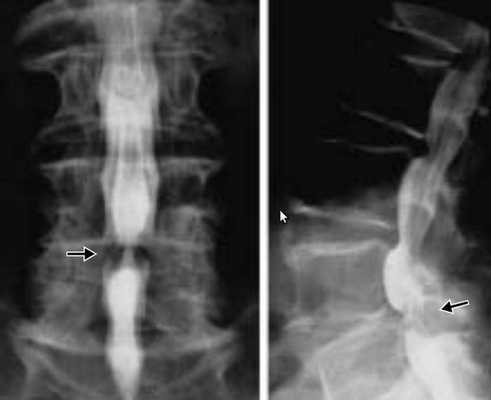

Стеноз позвоночного канала (спинальный стеноз) - симптомы и лечение

Стеноз позвоночного канала — это состояние, когда размеры позвоночного канала на поперечном срезе уменьшаются, либо уменьшаются размеры межпозвонковых отверстий, в результате чего сдавливается содержимое канала (спинной мозг, корешки) . Как правило, стеноз позвоночного канала выявляется на уровне нижних поясничных позвонков, реже — в шейном и грудном отделах позвоночника.

Диагностика стеноза позвоночного канала

Если появляются характерные жалобы, необходимы дополнительные методы обследования, которые позволят не только измерить размеры позвоночного канала, но и выявить причины, вызывающие компрессию нервных элементов внутри позвоночного канала.

- рентгенография пояснично-крестцового отдела позвоночника;

- компьютерная томография (КТ);

- магнитно-резонансная томография (МРТ).

Позвоночный стеноз диагностируют по совокупности выявленных признаков сужения позвоночного канала при наличии характерных клинических данных.